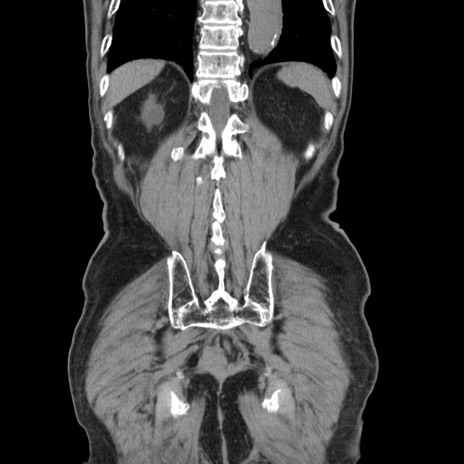

症例24(冠状断像)

矢状断像